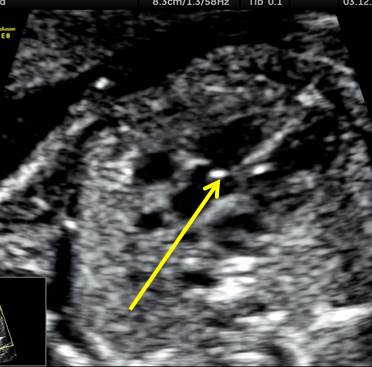

У плода атрезия митрального клапана, гипоплазия левого желудочка, гипоплазия аорты, реверсный кровоток в дуге аорты.

- В 4-камерном срезе обращает на себя внимание отсутствие тока крови через митральный клапан.

- В срезе через 3 сосуда просвет аорты значительно меньше просвета легочного ствола. В клипах и на изображениях мы видим разнонаправленные потоки крови в магистральных сосудах: антеградный в легочном стволе и ретроградный в аорте, то есть кровь поступает в аорту не из левого желудочка, а через артериальный проток.

- В сагиттальном срезе через дугу аорты и дугу артериального протока мы тоже видим разнонаправленные потоки крови.